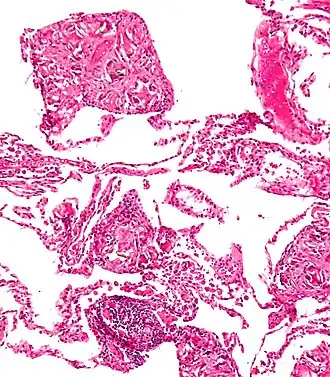

Гистологическая картина характеризуется развитием диффузного межуточного склеротического процесса в лёгких с поражением альвеолярных перегородок, перибронхиальной и периваскулярной ткани. На местах скопления тальковой пыли отмечаются склеротические узелки с наличием гистиоцитарных, лимфоидных элементов и гигантских клеток. «Тальковые узелки» не имеют тенденции к слиянию, а гиалиноз соединительной ткани выражен слабо[10].